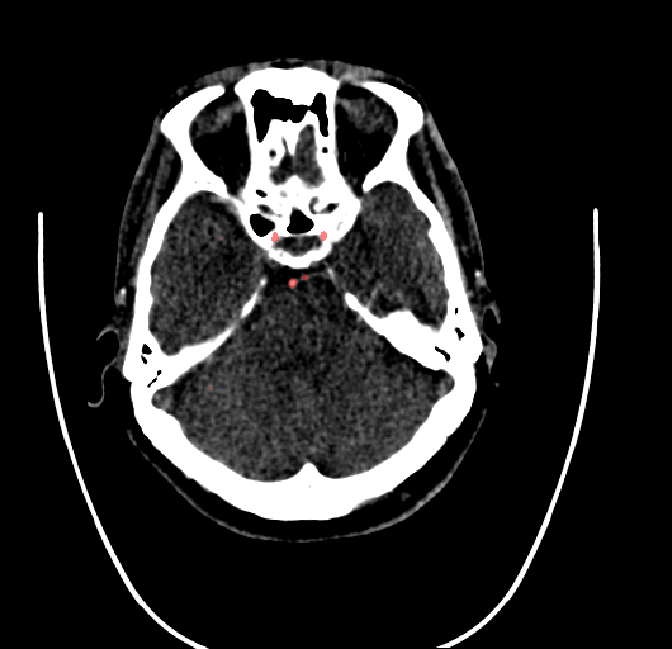

Refer to caption

Figure 4.4: Segmentations on regions near internal carotid arteries. Unaltered image (left). No pretrain model (mid-left). Fine-tuned model (mid-right). Hand-labeled ground truth (right).

In the other hand, it should be noted that fine-tuned models suffered from false positives more often than models with no pre-training. The fine-tuned models appeared to occasionally segment regions near the skull, which although similar in intensity to vessels, had no resemblance in terms of shape. Examples of this are seen in Figure 4.4 near the occipital bone and near the right temporal bone. Examples of oversegmentation were observed to happen commonly around the internal carotid arteries. This is likely due to the amount of contact surface between the artery and the surrounding bone. There was also a tendency for all model conditions to segment bone regions that were similar in shape to large vessels (Figures 4.3 and 4.4). Bone structures in such regions have similar pixel intensities to the arteries transporting contrast material, which could explain the source of confusion for a model.

To our surprise, the models were able to occasionlly segment the shape of the internal carotid arteries correctly despite no boundary being visible to the naked eye between the vessel wall and the surrounding bone structure. An example of this can be seen in the fine-tuned model in Figure 4.3.